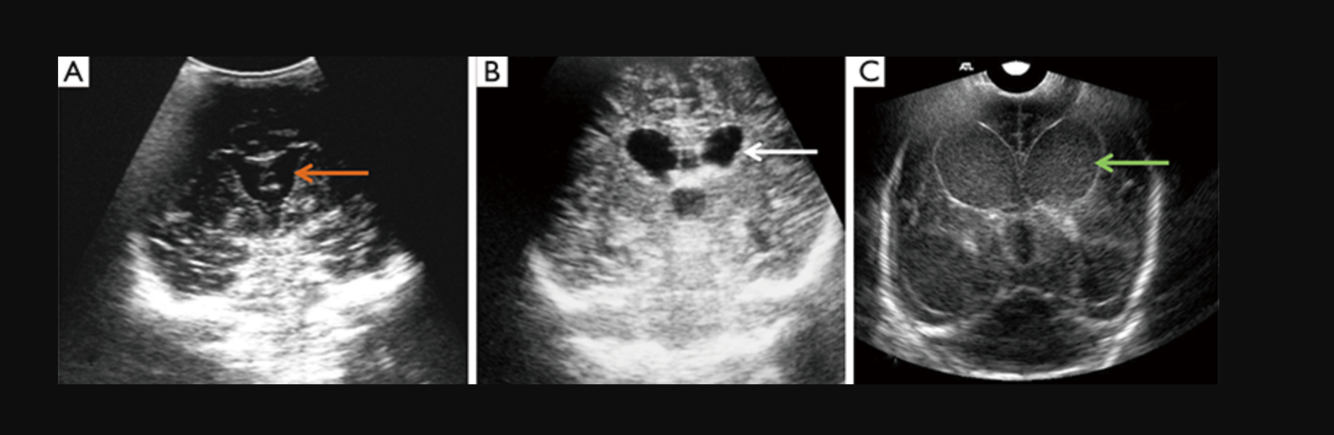

Antenatal ultrasound

With increased availability and quality of antenatal ultrasound, the diagnosis is increasingly made prior to delivery. Antenatal detection is however mostly reported late in pregnancy (3rd trimester).

The dilated median prosencephalic vein (MPV) appears as an anechoic structure in the midline posteriorly and demonstrates prominent flow on Doppler examination. Shunting may lead to complications such as hydrops fetalis or fetal cardiomegaly.